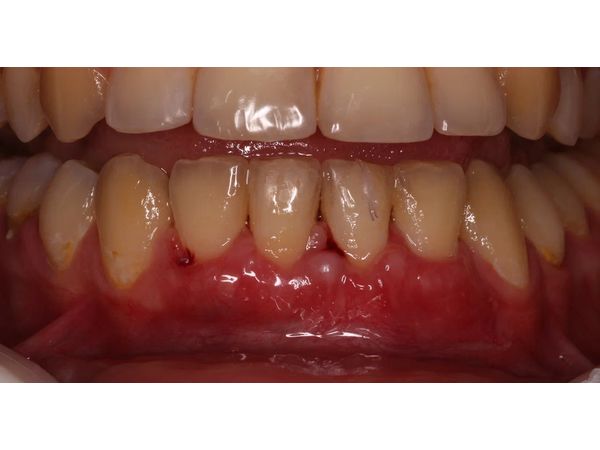

Через неделю провели промежуточный осмотр, чтобы снять мягкие зубные отложения, через 2 недели сняли швы и гигиенически обработали поверхность зубов. Донорская зона заживала вторичным натяжением (грануляционной тканью).

Уже через 2 недели рецессия была устранена, а сосочек восстановлен. Дубликатура сохранилась, но пациентку она не беспокоила.